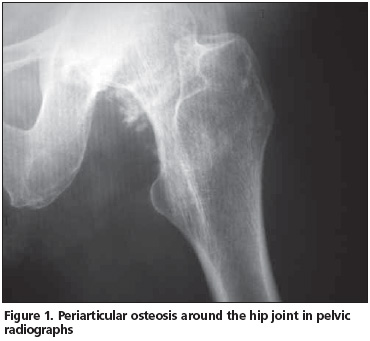

A 52-year-old female patient was admitted to our clinic with pain, swelling and limitation of motion in her left leg. It was learned that the patient underwent aortic valve replacement and aortoiliac bypass approximately 20 days ago. The patient was cooperative. She was brought to the outpatient clinic by stretcher. She described pain in the left thigh and leg, which increased when she tried to move her leg. Swelling was present approximately 5 cm above the left knee joint. There was no color change or spasticity. Deep tendon reflexes were normoactive. The knee and hip joint range of motion could not be evaluated because of severe pain. Laboratory examinations results were as follows: hemoglobin (Hb): 10.2 g/dl, hematocrit (Hct): 32%, white blood cell (WBC): 5200/mm3, platelet: 30, 000/mm3, erythrocyte sedimentation rate: 22 mm/h, C-reactive protein: 4, and alkaline phosphatase (ALP): 460 U/L. Other biochemical tests and urine tests were within normal limits. Periarticular osteosis areas were seen around the left hip joint in pelvic radiographs (Figure 1). No new bone formation around the knee joint was seen on the X-ray (Figure 2). In the left hip and knee bone scintigraphy, increased osteoblastic activity was considered as heterotopic ossification developing in two separate regions. The patient was started on passive joint range of motion exercises for the knee and hip joint. Cold pack on the hip and knee joints three times daily for 20 minutes was recommended. Indomethacin (75 mg/day) and etidronate disodium (400 mg/day) were given. Control of pain and decreased swelling were achieved after approximately 20 days, and increase in range of motion was detected. Joint range of motion and stretching exercises were continued with the rehabilitation, and the patient was recommended to continue treatment with etidronate disodium for three months.